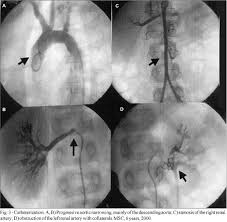

Demonstration Of Peripheral Pulmonary Stenosis And Supravalvular Aortic Stenosis By Different Cardiac Imaging Modalities In A Patient With Williams Syndrome Usefulness Of Noninvasive Imaging Studies International Journal Of Cardiology